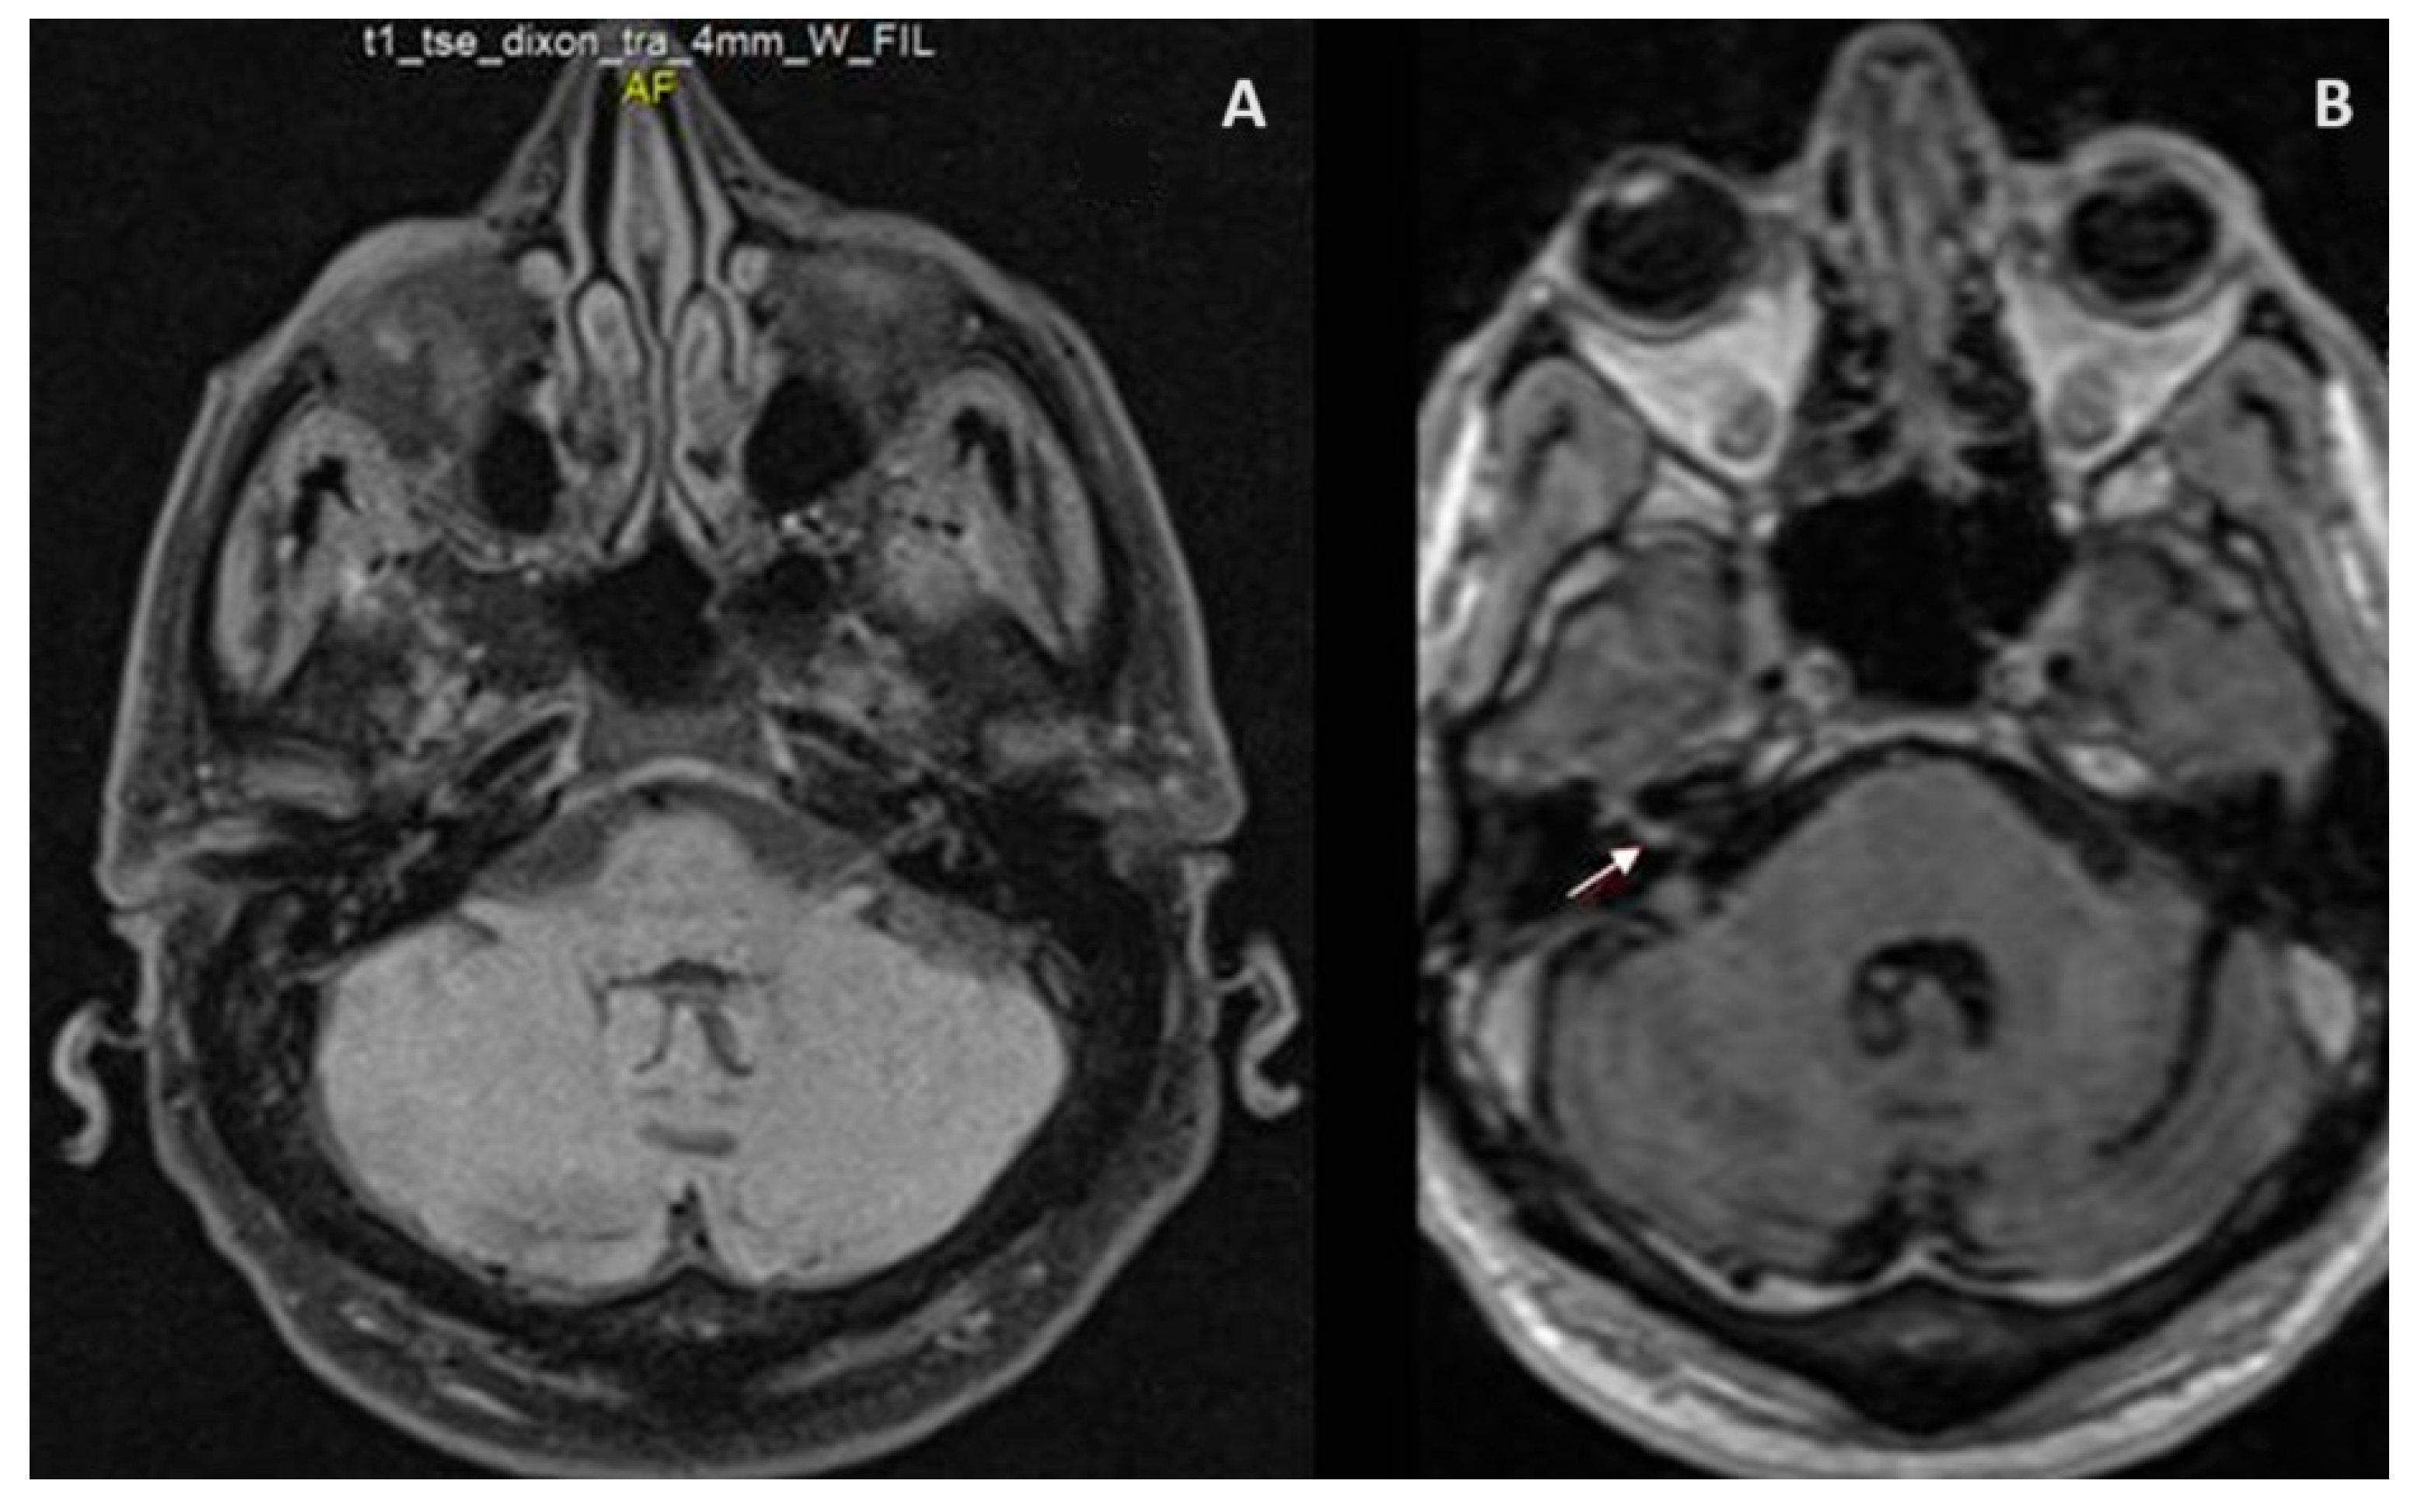

2. Case Presentation